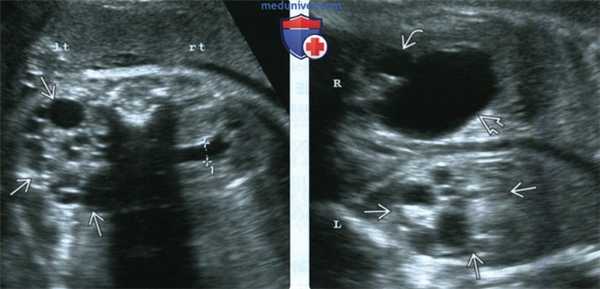

(Слева) УЗИ в поперечной плоскости. МКДП левой почки и незначительное расширение лоханки правой (калиперы). Левая почка не функционирует, поэтому важно следить за состоянием правой почки во время беременности и после рождения.

(Справа) УЗИ почек плода, фронтальная плоскость. Выраженное маловодие. МКДП левой почки и обструкция ЛМС правой (почечная лоханка и чашечки расширены). При тяжелой патологии второй почки прогноз неблагоприятный.